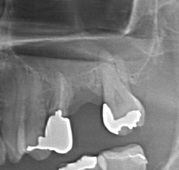

下顎管まで近いケースショートインプラントと垂直GBR(骨造成)で対応した →インプラント埋入

治療前

治療後

施術名 | インプラント埋入垂直GBR(骨造成) |

主訴 | 噛めない |

施術の副作用(リスク) | 感染脱落 |

施術の価格 | 1本GBR5万~10万(税抜き)+インプラント埋入補綴まで35万(税抜き) FGG5万 |

コメント | 下顎管まで近いケースショートインプラントと垂直GBR(骨造成)を同時に行いました |